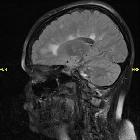

Dawson fingers are a radiographic feature of demyelination characterized by periventricular demyelinating plaques distributed along the axis of medullary veins, perpendicular to the body of the lateral ventricles and/or callosal junction. This is thought to reflect perivenular inflammation. They are a relatively specific sign for multiple sclerosis.

History and etymology

Dawson fingers are named after Scottish pathologist James Walker Dawson (1870-1927 ) who described the phenomenon on histopathological specimens in an article in 1916 , although the term "Dawson fingers" was brought forward by Charles Lumsden.